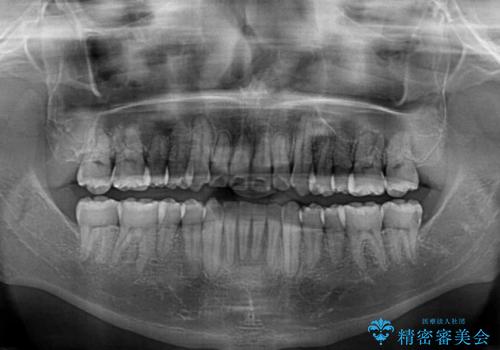

クロスバイトは、治療の過程で咬み合わせが大きく変化する期間があり、食事が取りにくくなってしまいます。

また、装置が対合歯と咬み合ってしまい、頻繁に脱落するなど、色々と面倒なことがあり、治療がスムーズに進まないことがあります。

デコボコが解消されると歯列が拡大される方向に動くため、出っ歯のような仕上がりとなることがあります。舌の突出癖を改善するトレーニングをしっかりと行っていただくことで、突出を抑制することができます。